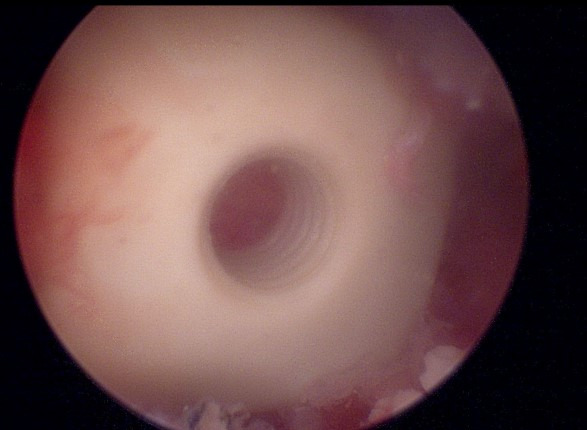

위 사진이 재수술을 2차례 하였던 병변의 모습입니다

디스크를 하나하나 제거하여 통증의 포인트를 찾아가구요

뼈이식까지 모두 진행한 이후에 케이지를 삽입할 준비를 하게 됩니다

내시경으로 환자분 체격에 맞는 케이지를 확인하고 삽입하게 됩니다.